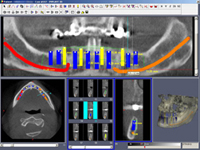

• Dokonalé vyšetření, stanovení diagnózy,naplánování ošetření - způsob, časový průběh,cena

• Zavedení implantátu do kosti čelisti

• Zahojení do kosti – 3-4měsíce(v některých případech i déle – doplňování kosti)

• Otisk situace v ústech a vytvoření modelu v laboratoři

• Zkouška zubní náhrady

• Předání definitivní náhrady